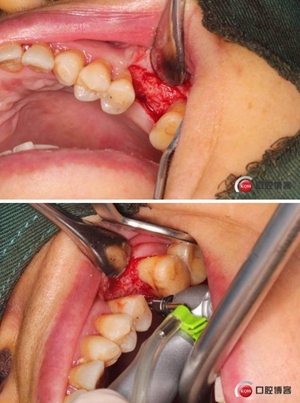

改良式外提升工具盒-外提 科貿(mào)嘉友收錄

大家好,我是梁老師的助理小依。由于梁老師每天手術(shù)檔期安排較滿,加上經(jīng)常出差講課,沒(méi)有時(shí)間整理病例 。為了方便大家更及時(shí)的了解梁老師最新手術(shù)動(dòng)態(tài),以后將由我為大家整理并推送梁老師最新經(jīng)典案例。案例文字旁白少,但圖片會(huì)盡量完整展示手術(shù)全過(guò)程,供大家學(xué)習(xí)參考。有任何問(wèn)題,可以留言,梁老師會(huì)親自為大家解答。感謝大家對(duì)梁老師的支持和關(guān)注!

六個(gè)月之后